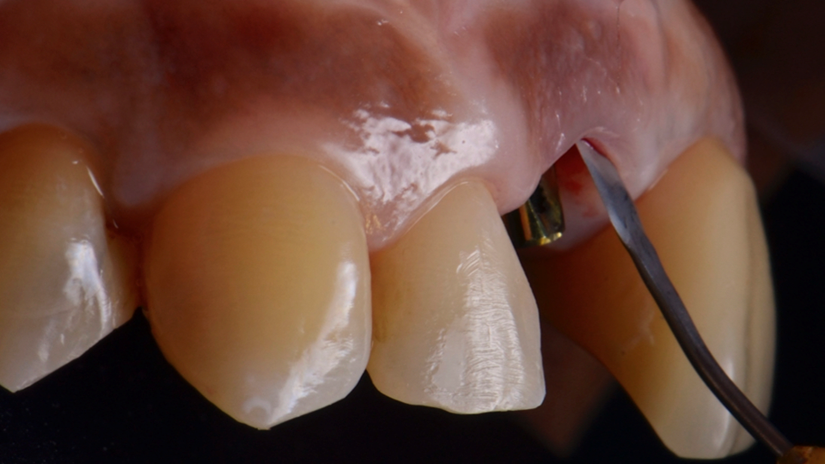

A região anterior da maxila é uma das áreas mais desafiadoras para reabilitação protética, principalmente quando se trata de implantes mal posicionados. Este caso clínico ilustra uma abordagem resolutiva para um implante vestibularizado na região do elemento 11, originalmente restaurado com um pilar reto tipo Smart de 4,5 mm, que inviabilizava a confecção de uma coroa parafusada esteticamente satisfatória.

A paciente apresentava queixas estéticas e funcionais. Após avaliação clínica e radiográfica, optou-se pela substituição do pilar reto por um pilar Ideale angulado de 17 graus e 3,3 mm de diâmetro. Esse componente mais estreito e angulado permitiu corrigir o eixo emergente da futura coroa, viabilizando o planejamento de uma prótese parafusada na região estética.